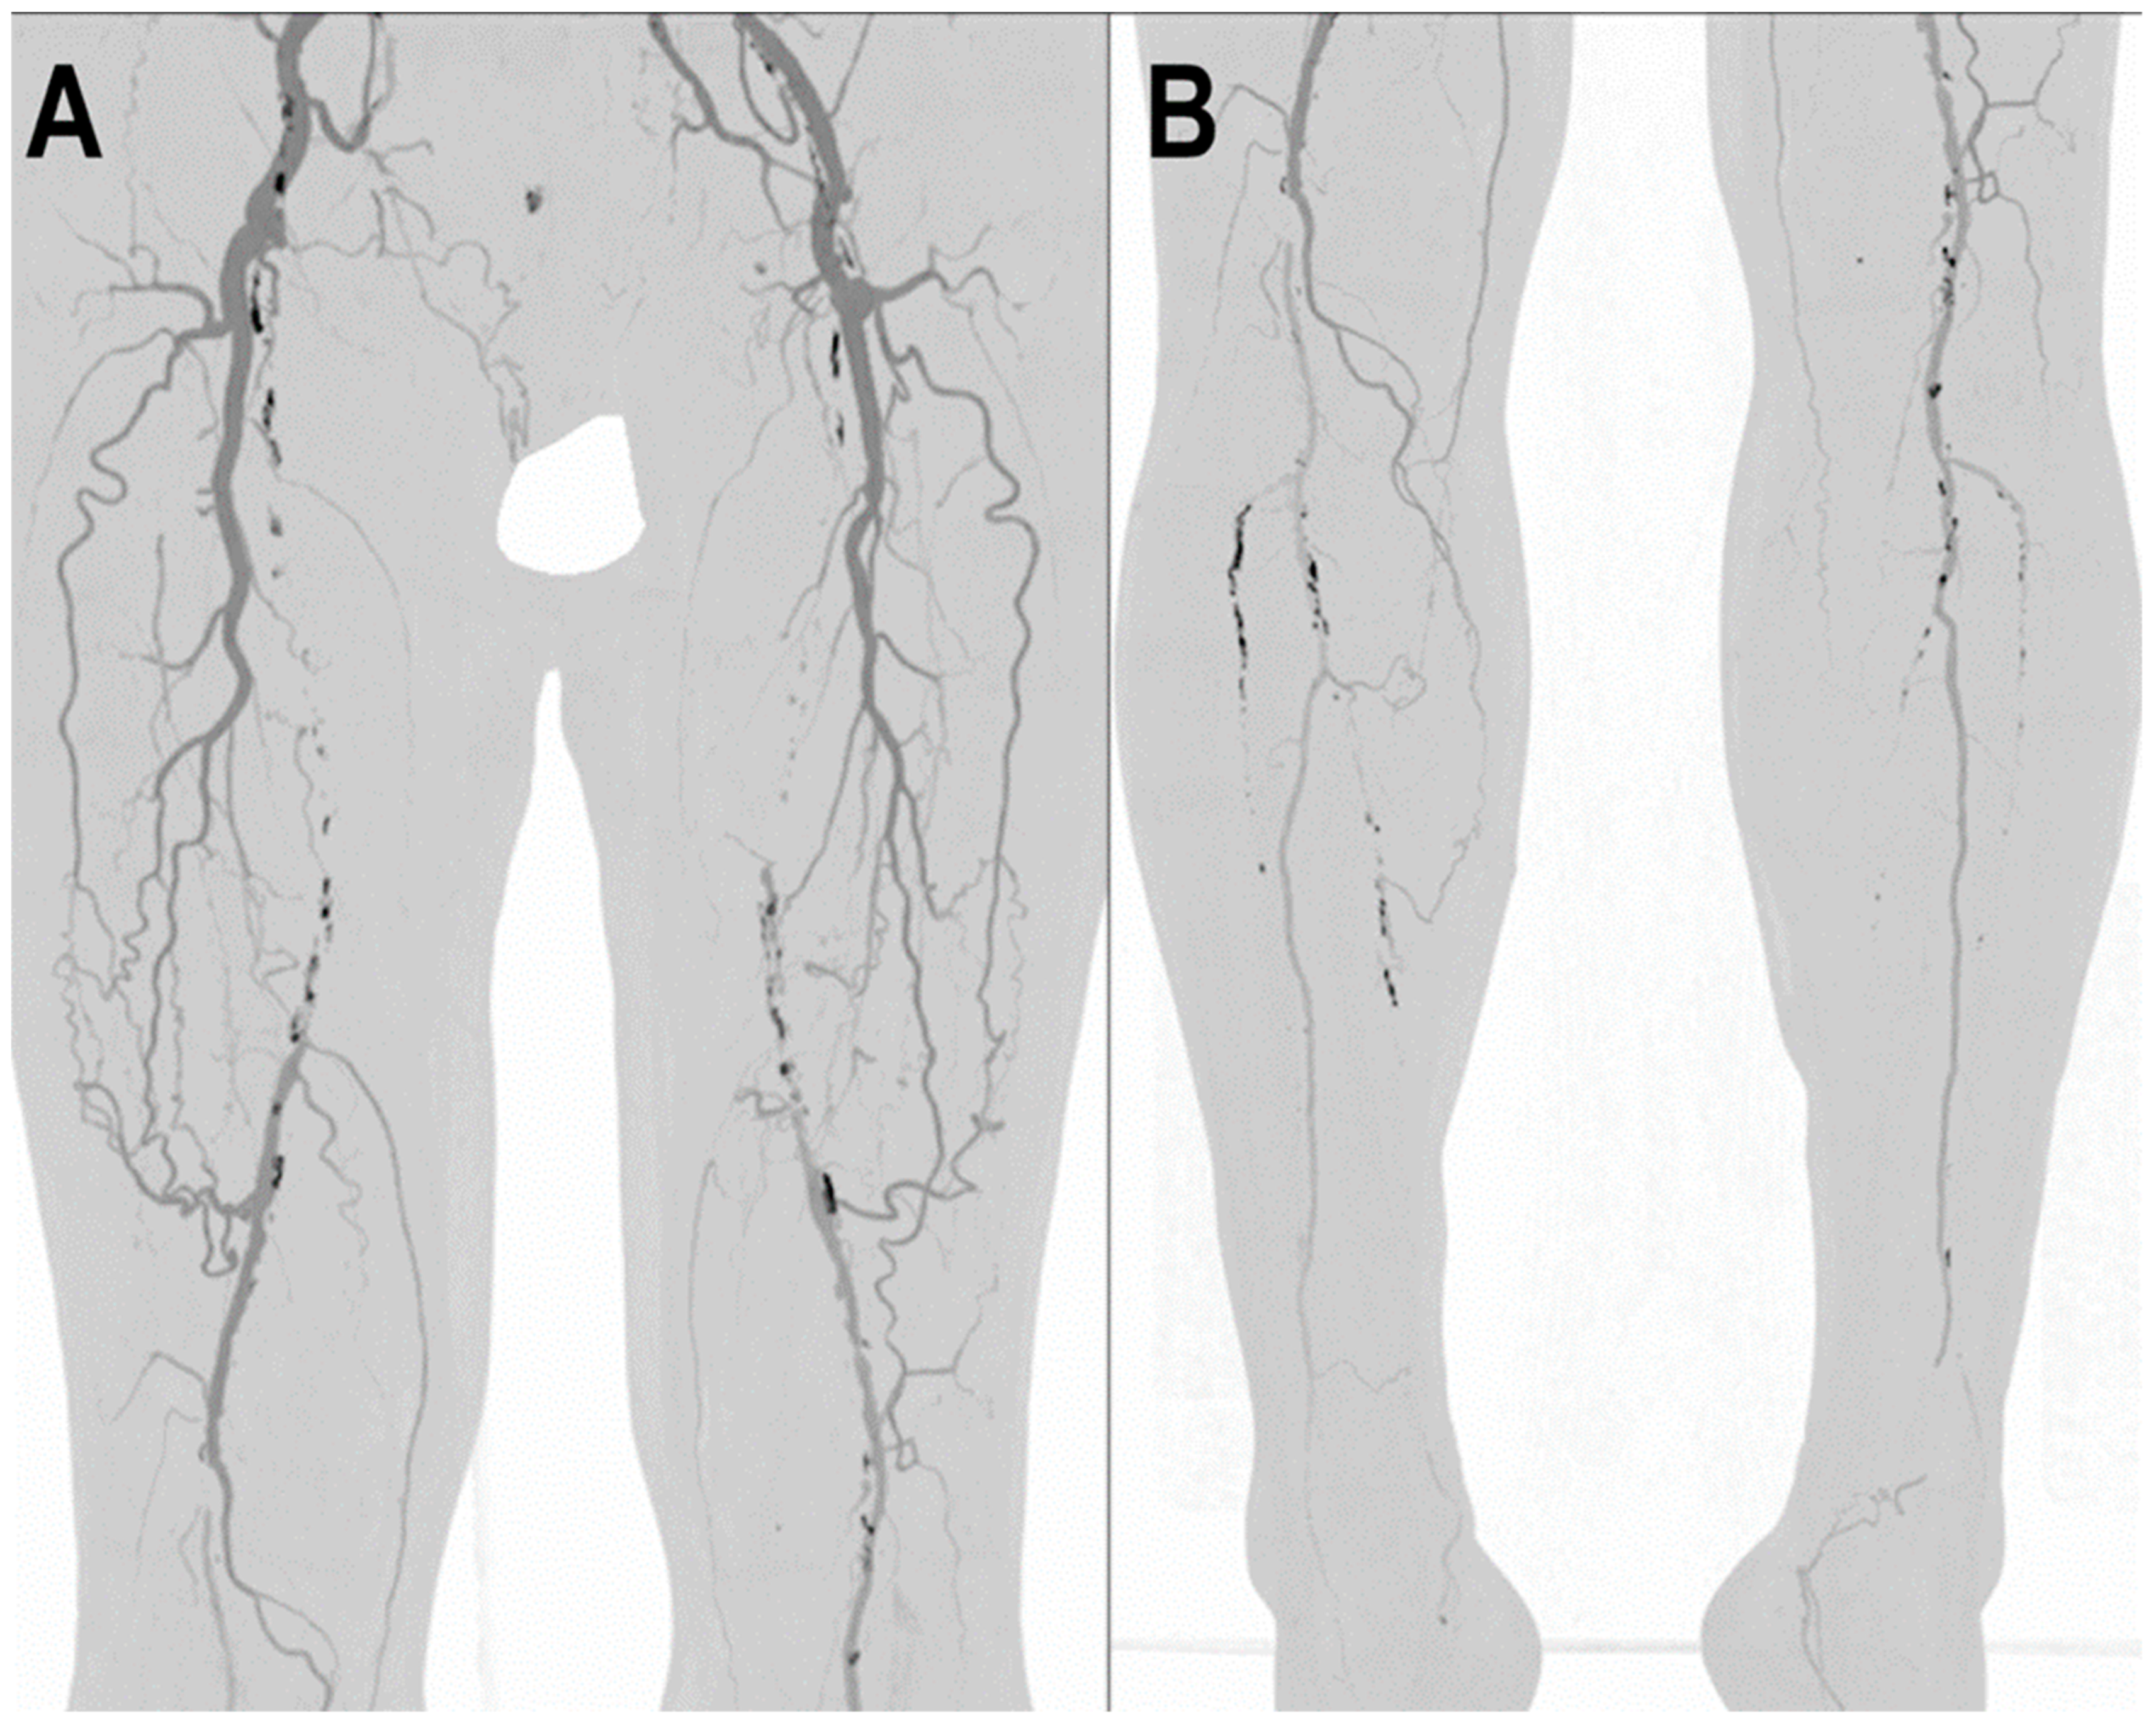

- Shwaiki, O.; Rashwan, B.; Fink, M.A.; Kirksey, L.; Gadani, S.; Karuppasamy, K.; Melzig, C.; Thompson, D.; D’Amico, G.; Rengier, F.; et al. Lower extremity CT angiography in peripheral arterial disease: From the established approach to evolving technical developments. Int. J. Cardiovasc. Imaging 2021, 37, 3101–3114. [Google Scholar] [CrossRef] [PubMed]

- Tanaka, R.; Yoshioka, K.; Takagi, H.; Schuijf, J.D.; Arakita, K. Novel developments in non-invasive imaging of peripheral arterial disease with CT: Experience with state-of-the-art, ultra-high-resolution CT and subtraction imaging. Clin. Radiol. 2019, 74, 51–58. [Google Scholar] [CrossRef]

- Leng, S.; Yu, Z.; Halaweish, A.; Kappler, S.; Hahn, K.; Henning, A.; Li, Z.; Lane, J.; Levin, D.L.; Jorgensen, S.; et al. Dose-efficient ultrahigh-resolution scan mode using a photon counting detector computed tomography system. J. Med. Imaging 2016, 3, 043504. [Google Scholar] [CrossRef]